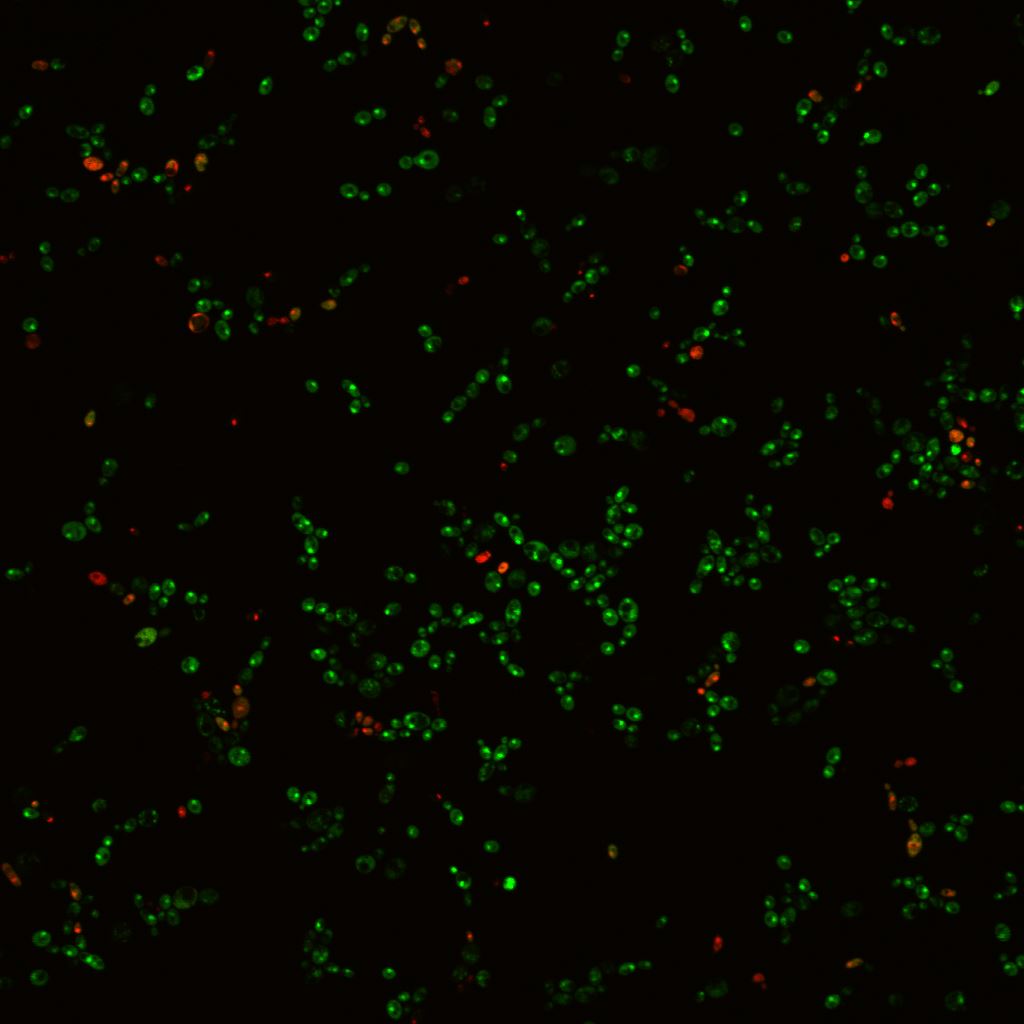

研究團隊發現紅紫素能有效抑制白色念珠菌在塑料表面生長及生成菌膜(也稱生物膜);它亦能破壞已生成熟之生物膜。相關研究結果已在國際期刋PLoS ONE發表。

研究報告指出,紅紫素大大減低白色念珠菌在塑料表面生成生物膜之能力,其效力呈濃度依賴關係。加入3µg/mL之的紅紫素可抑制生物膜之形成約44%;提高紅紫素之濃度至10µg/mL更可抑制生物膜之形成達約64%。然而,同等份量之紅紫素對抑制已形成之白色念珠菌生物膜之效用較差,分別為約6%及約37%。研究團隊表示已形成之生物膜結構非常緊密,增加其抗藥性。

研究團隊利用電子顯微鏡掃描白色念珠菌生物膜,發現加入3µg/mL之紅紫素能有效抑制生物膜之形成,並顯示構成生物膜之細胞主要呈現酵母菌狀態,由此證明該濃度之紅紫素足以抑制白色念珠菌轉化為菌絲狀態--另一種致病因子。研究團隊進一步確認紅紫素抑制白色念珠菌轉化為菌絲之效力在液體或固體培養基中並無差異。